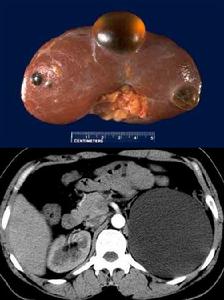

囊腫自腎實質產生,突出腎皮質表面,外觀呈藍色,但也可位於腎皮質深層或髓質。囊壁薄,為單層扁平上皮,囊內含清亮漿液性液體。囊壁厚而不光滑,液體為血性者,提示有惡變的可能,惡變率為3%-7%。位於下極的巨大腎囊腫,可壓迫輸尿管引起梗阻、積液和感染。本病的發生原因尚不完全清楚,可能與先天性腎小球、腎小管結構異常和後天性損傷感染有關。

單純性腎囊腫常累及腎下極。出現症狀的囊腫其直徑平均約為10厘米,但也有少數可大至充滿脅腹部。囊腫內通常含清亮琥珀色囊液。囊壁很薄,囊腫常呈“藍色圓頂”狀。偶可見囊壁鈣化。約5%的囊腫含血性囊液,其中半數囊壁上可能有乳頭狀癌。

單純性腎囊腫好發於腎臟表面,但也可位於深部。當一囊腫位於深部時,其囊壁就與腎盂及腎盞的上皮內壁緊連,要將它們分開十分困難,但囊腫並不與腎盂相通。鏡檢可發現囊壁有重度的纖維變性及玻璃變性,還可見到鈣化區域,鄰近腎組織也受壓發生纖維變性。